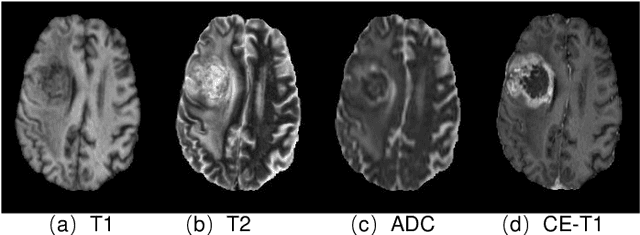

Abstract:Gadolinium-based contrast agents (GBCAs) have been widely used to better visualize disease in brain magnetic resonance imaging (MRI). However, gadolinium deposition within the brain and body has raised safety concerns about the use of GBCAs. Therefore, the development of novel approaches that can decrease or even eliminate GBCA exposure while providing similar contrast information would be of significant use clinically. For brain tumor patients, standard-of-care includes repeated MRI with gadolinium-based contrast for disease monitoring, increasing the risk of gadolinium deposition. In this work, we present a deep learning based approach for contrast-enhanced T1 synthesis on brain tumor patients. A 3D high-resolution fully convolutional network (FCN), which maintains high resolution information through processing and aggregates multi-scale information in parallel, is designed to map pre-contrast MRI sequences to contrast-enhanced MRI sequences. Specifically, three pre-contrast MRI sequences, T1, T2 and apparent diffusion coefficient map (ADC), are utilized as inputs and the post-contrast T1 sequences are utilized as target output. To alleviate the data imbalance problem between normal tissues and the tumor regions, we introduce a local loss to improve the contribution of the tumor regions, which leads to better enhancement results on tumors. Extensive quantitative and visual assessments are performed, with our proposed model achieving a PSNR of 28.24dB in the brain and 21.2dB in tumor regions. Our results suggests the potential of substituting GBCAs with synthetic contrast images generated via deep learning.